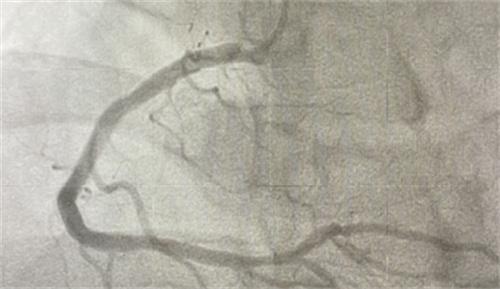

男青年小王25歲,年紀輕輕的就已經240斤了,在父母不斷的嘮叨之下,也開啟了自己的健身計劃,兩周時間當中成功減了10斤,為了給自己不斷加碼,在健身教練建議的運動量基礎之上,不斷繼續加練。結果在運動結束之后,隱隱覺得心臟有些不舒服,一到小區樓因為停電,所以又爬上了8樓,最終導致了急性心梗。

經過心血管醫生共同協力將生命通道打通,隨時候小王進入心血管病區的監護室,積極作出治療。目前恢復較為良好,心肌梗死指的是心臟供應血液的血管被堵塞,使得心臟在供血方面不足,特別是季節發生變化,高熱、寒冷、劇烈運動等,讓血管刺激收縮,還有感染等一些因素,很容易誘發急性心梗 通常心梗多發生在老年患者身上。目前45歲以下人群心梗發病率也在不斷的上升,這種病癥也纏上了年輕人。